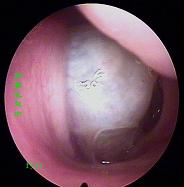

一、基本检查:1.前鼻镜检查。2.X线鼻泪管造影,明确有无并发鼻窦感染。